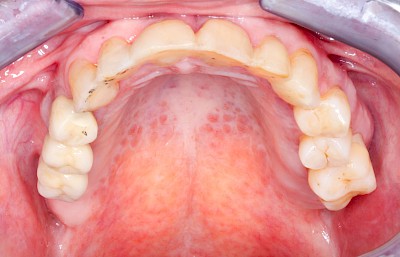

Einschmelzung & Geschwür

Das Risiko für Krebs der Mundhöhlen-Schleimhäute ist bei Menschen, die jahrelang übermäßig viel (Abusus) geraucht und erst recht lange übermäßig viel Alkohol getrunken haben, stark erhöht. Die Schleimhäute sehen dann aus wie "wildes Fleisch" – entweder mit blumenkohlartigen Auftreibungen oder aber es zeigen sich großflächige ungleichmäßig geformte Defekte und Einschmelzungen. Man spricht dann auch von einem Geschwür (Ulcus).

Entsteht der Krebs eher in tieferliegenden Schichten (z. B. im Bereich der Speicheldrüsen), sind die Auffälligkeiten nicht so deutlich. Hier fallen eher Seitenunterschiede links und rechts im Bereich der Mundhöhle auf. Auch plötzlich auftretendes und wiederholtes Nasenbluten, Einschränkungen der Atmung durch die Nase können Anzeichen für einen Tumor im Bereich der Nasen- oder Kieferhöhle sein.

Selten können auch Fibrome oder Druckstellen bei Zahnprothesen, wenn diese nicht erkannt und behandelt werden, in "wildes Fleisch" übergehen und hin zu bösartigen Tumoren entarten.

Bei allen diesen Auffälligkeiten ist eine sofortige (zahn-)ärztliche Abklärung zu veranlassen.